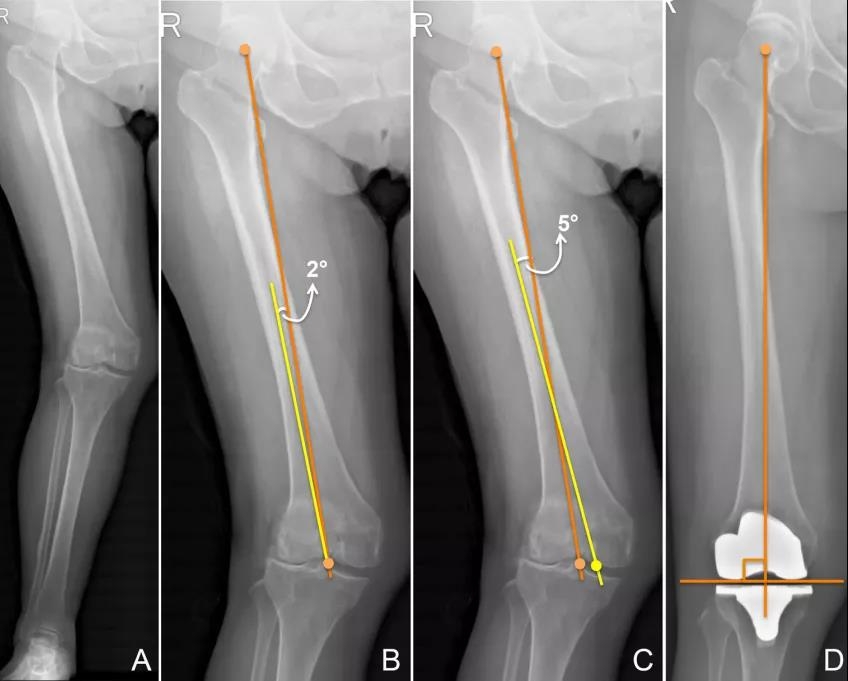

A.股骨外髁发育不良导致的外翻膝。

B.从机械轴和关节线的焦点(膝关节中点)引出解剖轴来确定VCA是不合适的,因为此时的解剖轴已经不是真正的解剖轴了。如果髓内杆始终从股骨远端中点插入,而为了避免脂肪栓塞综合征的发生而扩大了入髓口,则髓内杆所运动的通道非常狭窄就会被迫偏离术前所设计的路径。

C.当正确的划出机械轴和解剖轴,则这两个轴线会在股骨干的远端相交,而其夹角就是VCA角(本例的VCA角为5°);而解剖轴和股骨远端关节线的焦点经常位于关节中点的内侧。

D. 术后X片可见根据这个技术测量的VCA做出来的手术的股骨假体远端关节线与股骨机械轴更加垂直。